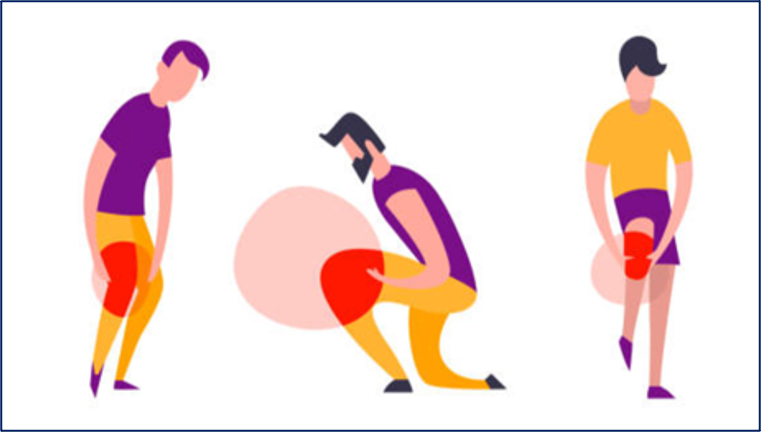

由于我国全民健身运动的普及、体育水平的加强,以及体育运动中动作难度的增加,目前运动损伤发生率明显增高。

前交叉韧带损伤

很多患者在听了我们的诊断意见之后,对于要做手术很疑虑,因为韧带损伤后,患者通常还能走路和日常生活,只不过在运动时候常常扭伤。很多患者说:大不了我不再运动了。殊不知,正是这样的误解造成日后难以弥补的恶果。

失去了前交叉韧带的关节,前后以及旋转不稳定,关节总是晃来晃去,必然导致关节内其它结构,如半月板,软骨的磨损,不仅在运动时反复扭伤,而且在日常生活中也会不断地磨损着关节,导致关节退变,也就是机器老化。